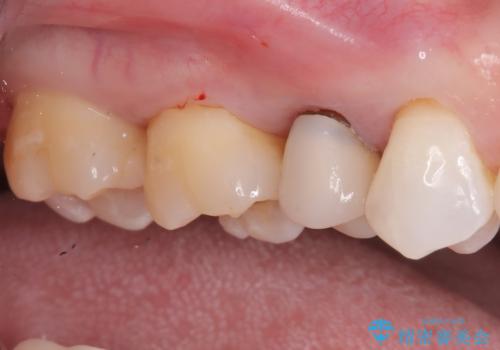

【根管治療】ズーンと痛い歯の治療。

- 奥歯付近がジーンと痛いことを主訴に来院されました。

左上7番の歯は、歯髄検査にて反応を示し、歯周ポケットはありませんでした。

親知らず抜歯を行い、痛みの変化や歯根吸収の有無を確認したのち、抜髄処置を行っています。

症状改善し、遠心の骨の回復も認めます。